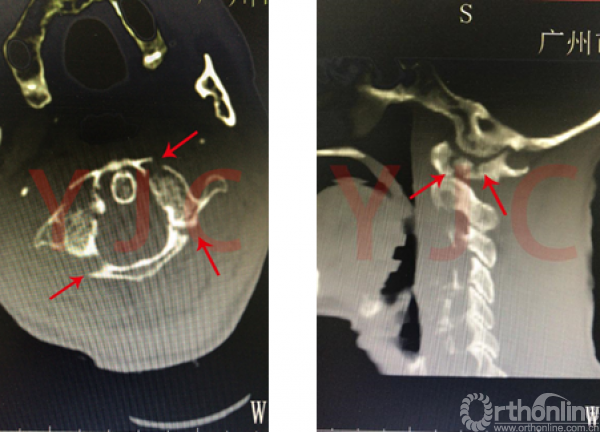

家住广东白云区江高的邝奶奶今年80岁了,这天下午起床时她从床上跌落,头部着地,当即动弹不得,脖颈稍一活动就剧痛无比。家人发现奶奶摔倒在地,立刻拨打了120,送至当地医院行CT检查,发现邝奶奶发生寰椎(上颈椎)爆裂性骨折。

寰椎爆裂性骨折,又称Jefferson骨折,是指寰椎在纵向暴力作用下发生多处骨折,依据不同的受力特点可引起不同的临床症状及后果。由于寰椎椎管内的脊髓毗邻人体呼吸、心跳中枢,此处骨折如果并发颈脊髓神经损伤,严重者可能在送院之前便已死亡。幸运的是大部分寰椎爆裂性骨折病人其寰椎的骨折块是向外侧分离移位的,对颈脊髓神经损害并不严重,可能仅表现为枕颈部疼痛和颈部活动障碍,神经瘫痪症状轻微。但在这种情况下,头颅与颈椎之间存在明显不稳定性,如不及时固定处理,极有可能发生继发性高位颈脊髓损伤,严重时可能引起瘫痪甚至死亡。